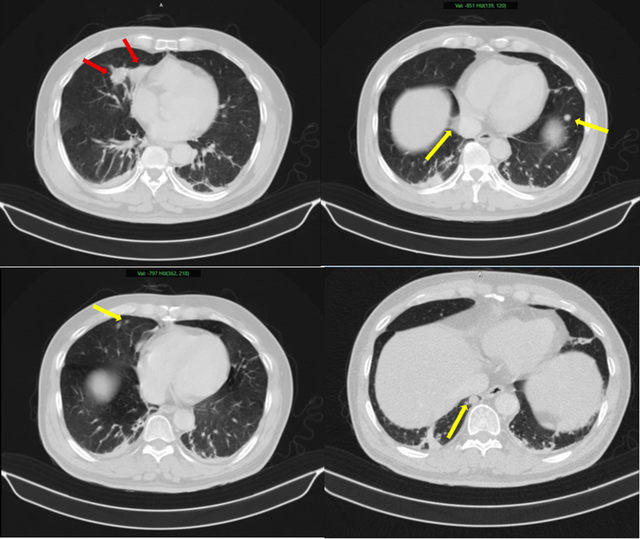

Hình ảnh 2 khối u bờ đa cung ở nhu mô thùy giữa phổi phải, dính vào màng phổi trung thất (mũi tên đỏ) kèm nhiều nốt đặc nhỏ rải rác nhu mô phổi hai bên (mũi tên vàng) gợi ý tổn thương thứ phát. Ảnh: BV Bạch Mai.